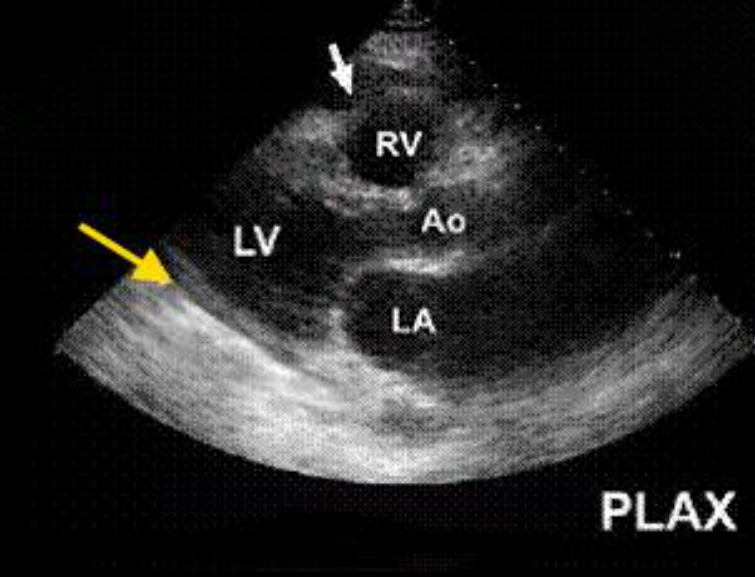

Как выглядит доля Риделя на УЗИ печени